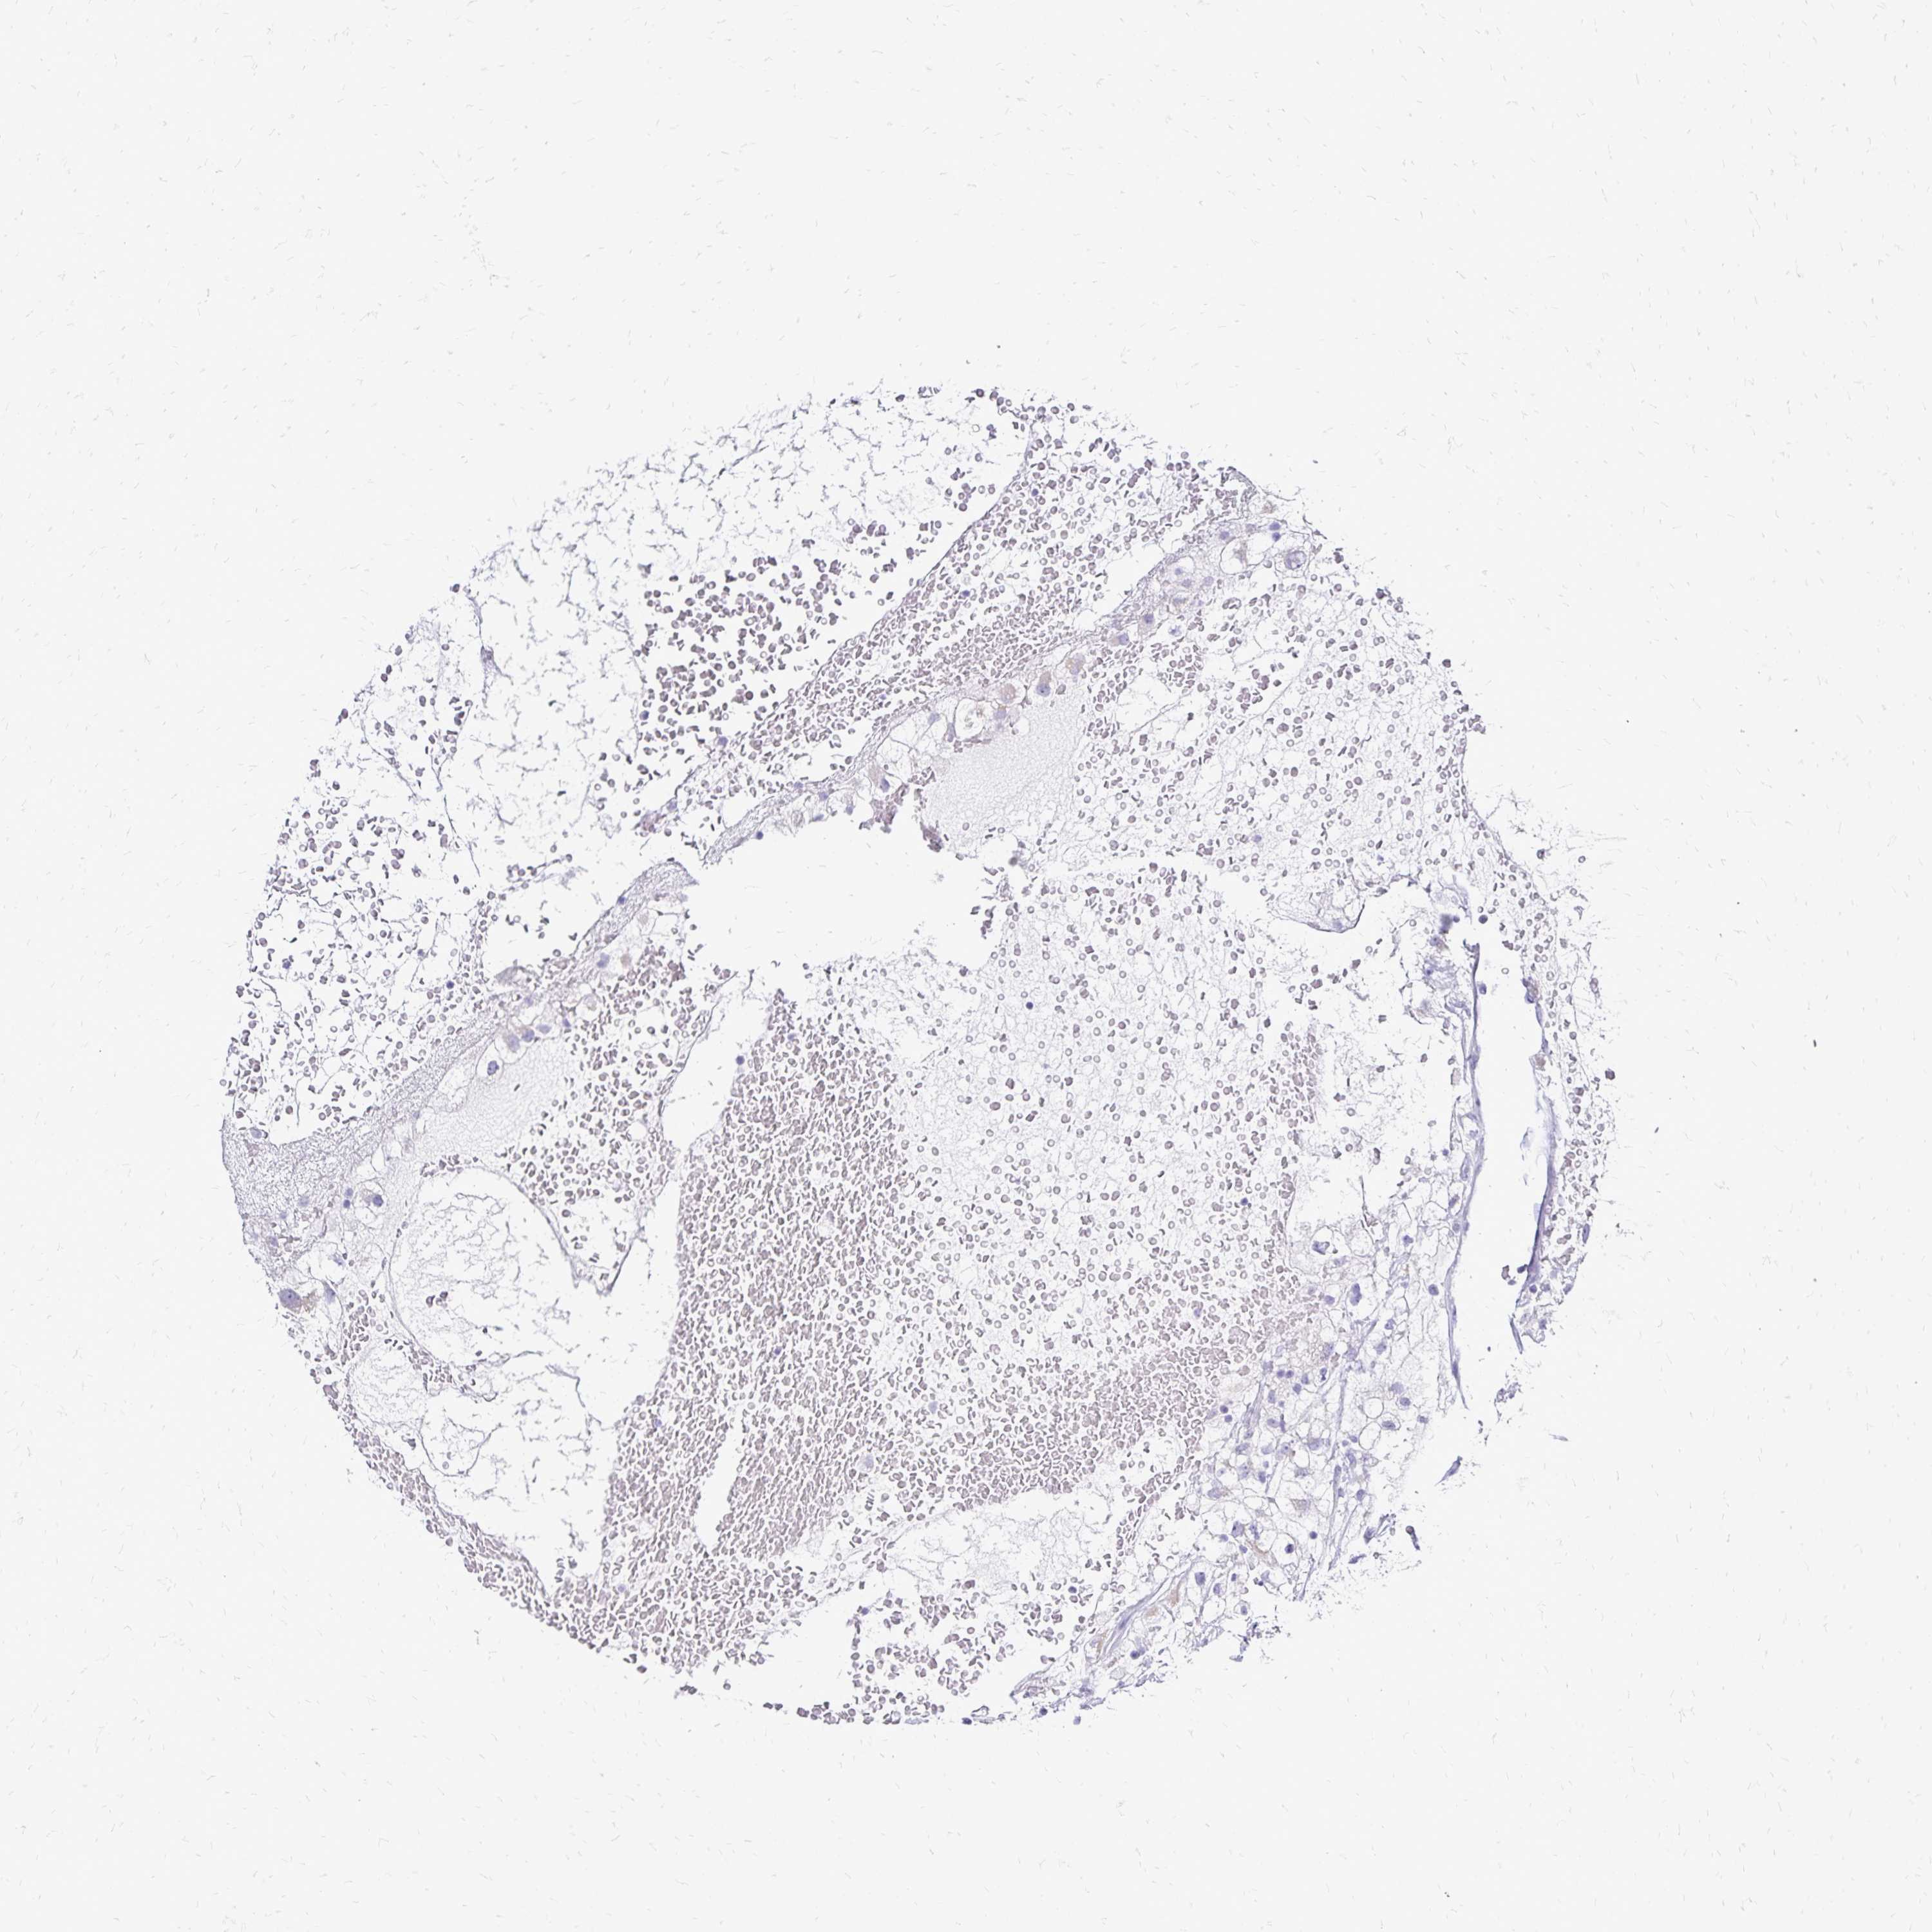

KIDNEY RENAL PAPILLARY CELL CARCINOMA (TCGA) - Interactive survival scatter ploti

The Survival Scatter plot shows the clinical status (i.e. dead or alive) for all individuals in the patient cohort, based on the same data that underlies the corresponding Kaplan-Meier plots. Patients that are alive at last time for follow-up are shown in blue and patients who have died during the study are shown in red.

The x-axis shows the expression levels (FPKM) of the investigated gene in the tumor tissue at the time of diagnosis. The y-axis shows the follow-up time after diagnosis (years). Both axes are complimented with kernel density curves demonstrating the data density over the axes. The top density plot shows the expression levels (FPKM) distribution among dead (red) and alive patients (blue). The right density plot shows the data density of the survived years of dead patients with high and low expression levels respectively, stratified using the cutoff indicated by the vertical dashed line through the Survival Scatter plot. This cutoff is automatically defined based on the FPKM cutoff that minimizes the p-score. The cutoff can be changed by dragging the vertical line or by entering a cutoff value in the square labeled "Current cut-off".

Under the Survival Scatter plot the p-score landscape (black curve; left axis) is shown together with dead median separation (red curve; right axis). Dead median separation is the difference in median mRNA expression between patients who have died with high and low expression, respectively. It is calculated as follows: median FPKM expression of dead patients with high expression - median FPKM expression of dead patients with low expression. This is intended to aid the user in visually exploring custom cutoffs and the associated p-scores and dead median separation.

Individual patient data is displayed and can be filtered by clicking on one or more of the category buttons on the top of the page. Categories describing expression level and patient information include: high, low, alive, dead, female, male and tumor stages. The scale of the x-axis can be toggled between linear and log-scale by clicking on the "x log" button. Mouse-over function shows TCGA ID, patient information and mRNA expression (FPKM) for each patient.

& Survival analysisi

Kaplan-Meier plots summarize results from analysis of correlation between mRNA expression level and patient survival. Patients were divided based on level of expression into one of the two groups "low" (under cut off) or "high" (over cut off). X-axis shows time for survival (years) and y-axis shows the probability of survival, where 1.0 corresponds to 100 percent.

CCDC39 is not prognostic in Kidney Renal Papillary Cell Carcinoma (TCGA)

Best expression cut offi

: 0.03